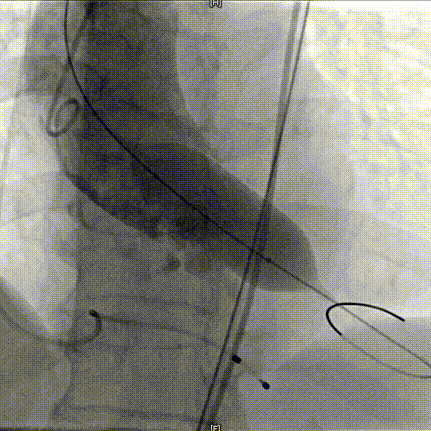

术中20mm球囊预扩可见轻微腰征,轻微瓣周漏,左冠充盈速度减慢,为保证患者安全,决定行冠脉保护,预防冠脉阻挡风险。选择AV26瓣膜,TaurusElite AV26瓣膜送至主动脉弓,输送系统轻松过弓及跨瓣,精准定位无冠窦最低点。

TaurusElite AV26瓣膜第一次释放定位位置接近瓣环,李怡教授准确定位判断,零位释放,瓣膜在手术计划的位置牢牢站稳了!手术过程行云流水,团队配合默契,操作细致熟练,主动脉根部造影及食道超声均只有少量瓣周漏;压差由术前的100mmHg直线下降到术后的5mmHg以内,TaurusElite首秀成功!